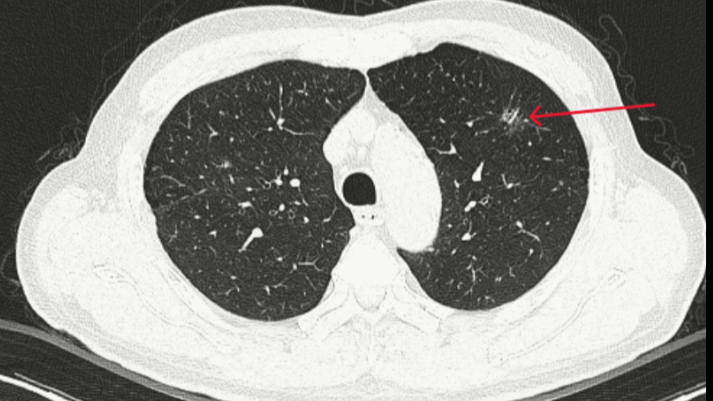

Thùy trên phổi trái có đám tổn thương kính mờ, bờ tua gai kích thước 10x13mm.

Bệnh nhân được chẩn đoán theo dõi ung thư thùy trên phổi trái cT1N0M0. Tổn thương phổi trên CT được sử dụng AI để phân tích, xác suất nốt kính mở ở thùy trên phổi trái là tổn thương ác tính khoảng 97%. Bệnh nhân được hội chẩn hội đồng có chỉ định phẫu thuật.